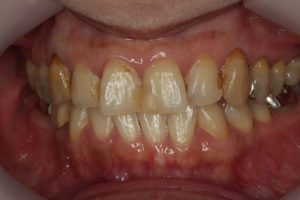

院長のコメント 1年間お疲れさまでした。たくさん治療しましたが、「あっけなくおわりました。」とおっしゃって頂きありがとうございました。当院ではお一人1時間でお約束をお取りしていますので、20分や30分で細かく分けて治療するのに比べ、無駄がなく効率よく進みます。 さらに、治療用の椅子は1台(メインテナンス用の椅子がもう1台)しか置いていませんので、私はお一人の治療に1時間集中できますから、なおさら治療は進みます。 ただ、決して急いでいる訳ではなく、じっくり治療をしているのですが、一つ一つ確実にステップを踏むとミスが少なくなり、その結果治療も早く進んでいくのです。 さて、この患者さんは、ブリッジをやり直す時にそのままブリッジにするかインプラントにするかとても迷われていたのですが、最終的にはインプラントを選択されました。アンケートにもありますように、皆さんが考えている程インプラント治療は痛みを伴うものではありません。今回のケースでも、全く痛みはなく痛み止めを飲むこともなかったそうです。

最後に、術前・術後のお写真をご紹介します。